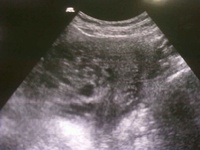

Molar pregnancies

Ultrasound showing multiple cystic areas in the uterine cavity giving a "snowstorm appearance" suggestive of molar pregnancy.

Nigam A, Kumari A, Gupta N. Negative urine pregnancy test in a molar pregnancy: is it possible? Case Reports 2014;2014:bcr2014206483.